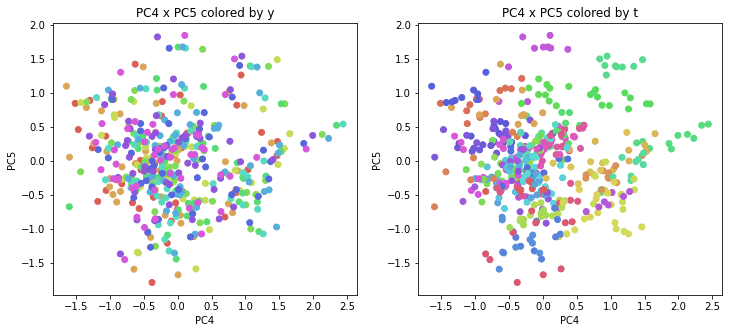

PCAの結果の第n主成分をPCnと表記します。

医療費データの場合と同様に、PCAの結果を見やすく表示するため、seabornのカラーパレットを使って、年月別、都道府県別に色分けして図示してみます(左側が年月別に色分け、右側が都道府県別に色分け)。PC1~PC8まで表示しました。

医療費データの場合ほどはっきりとはしていませんが、PC2が概ね時間の経過を表す成分で、残りの成分が時点によって変わらない地域の特徴を表す成分となっているようです。

また、PC1×PC3を見ると、47沖縄が他の都道府県からかなり離れたところに位置しており、沖縄の地域差が際立っているのが分かります。これは、以前別の記事で年齢階級のない健診データでPCAを実行した場合と似た結果となっています。

今回は、医療費データと同様に、健診データ240次元についてPCAを実行してみました。PCAの結果、医療費データの場合ほどはっきりしとはしていませんが、第2主成分が概ね時間の経過を表す成分で、時間軸に沿った全体的な動き(全国的な動き)を表しており、それ以外の成分が地域の特徴を表す成分で、この10年間あまり変わっていないことがわかりました。